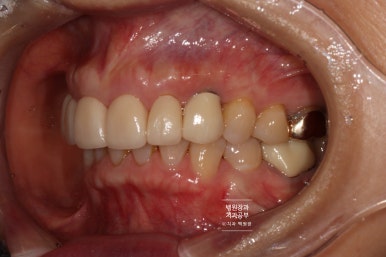

측면에서 보아도 자연스러운 외형을 관찰할 수 있고, 이차 충치가 생기거나 잇몸질환이 생기는 것을 방치하기 위하여 4개의 치아와 2개의 임플란트 모두 크라운을 따로따로 제작하였습니다.

그래야 치실을 사용하실 수 있어 구강위생관리가 가능해집니다!!!! 앞니 크라운을 다 붙여서 만드는 것은 정말 왠만하면 피하는 것이 좋습니다. ㅠㅠ